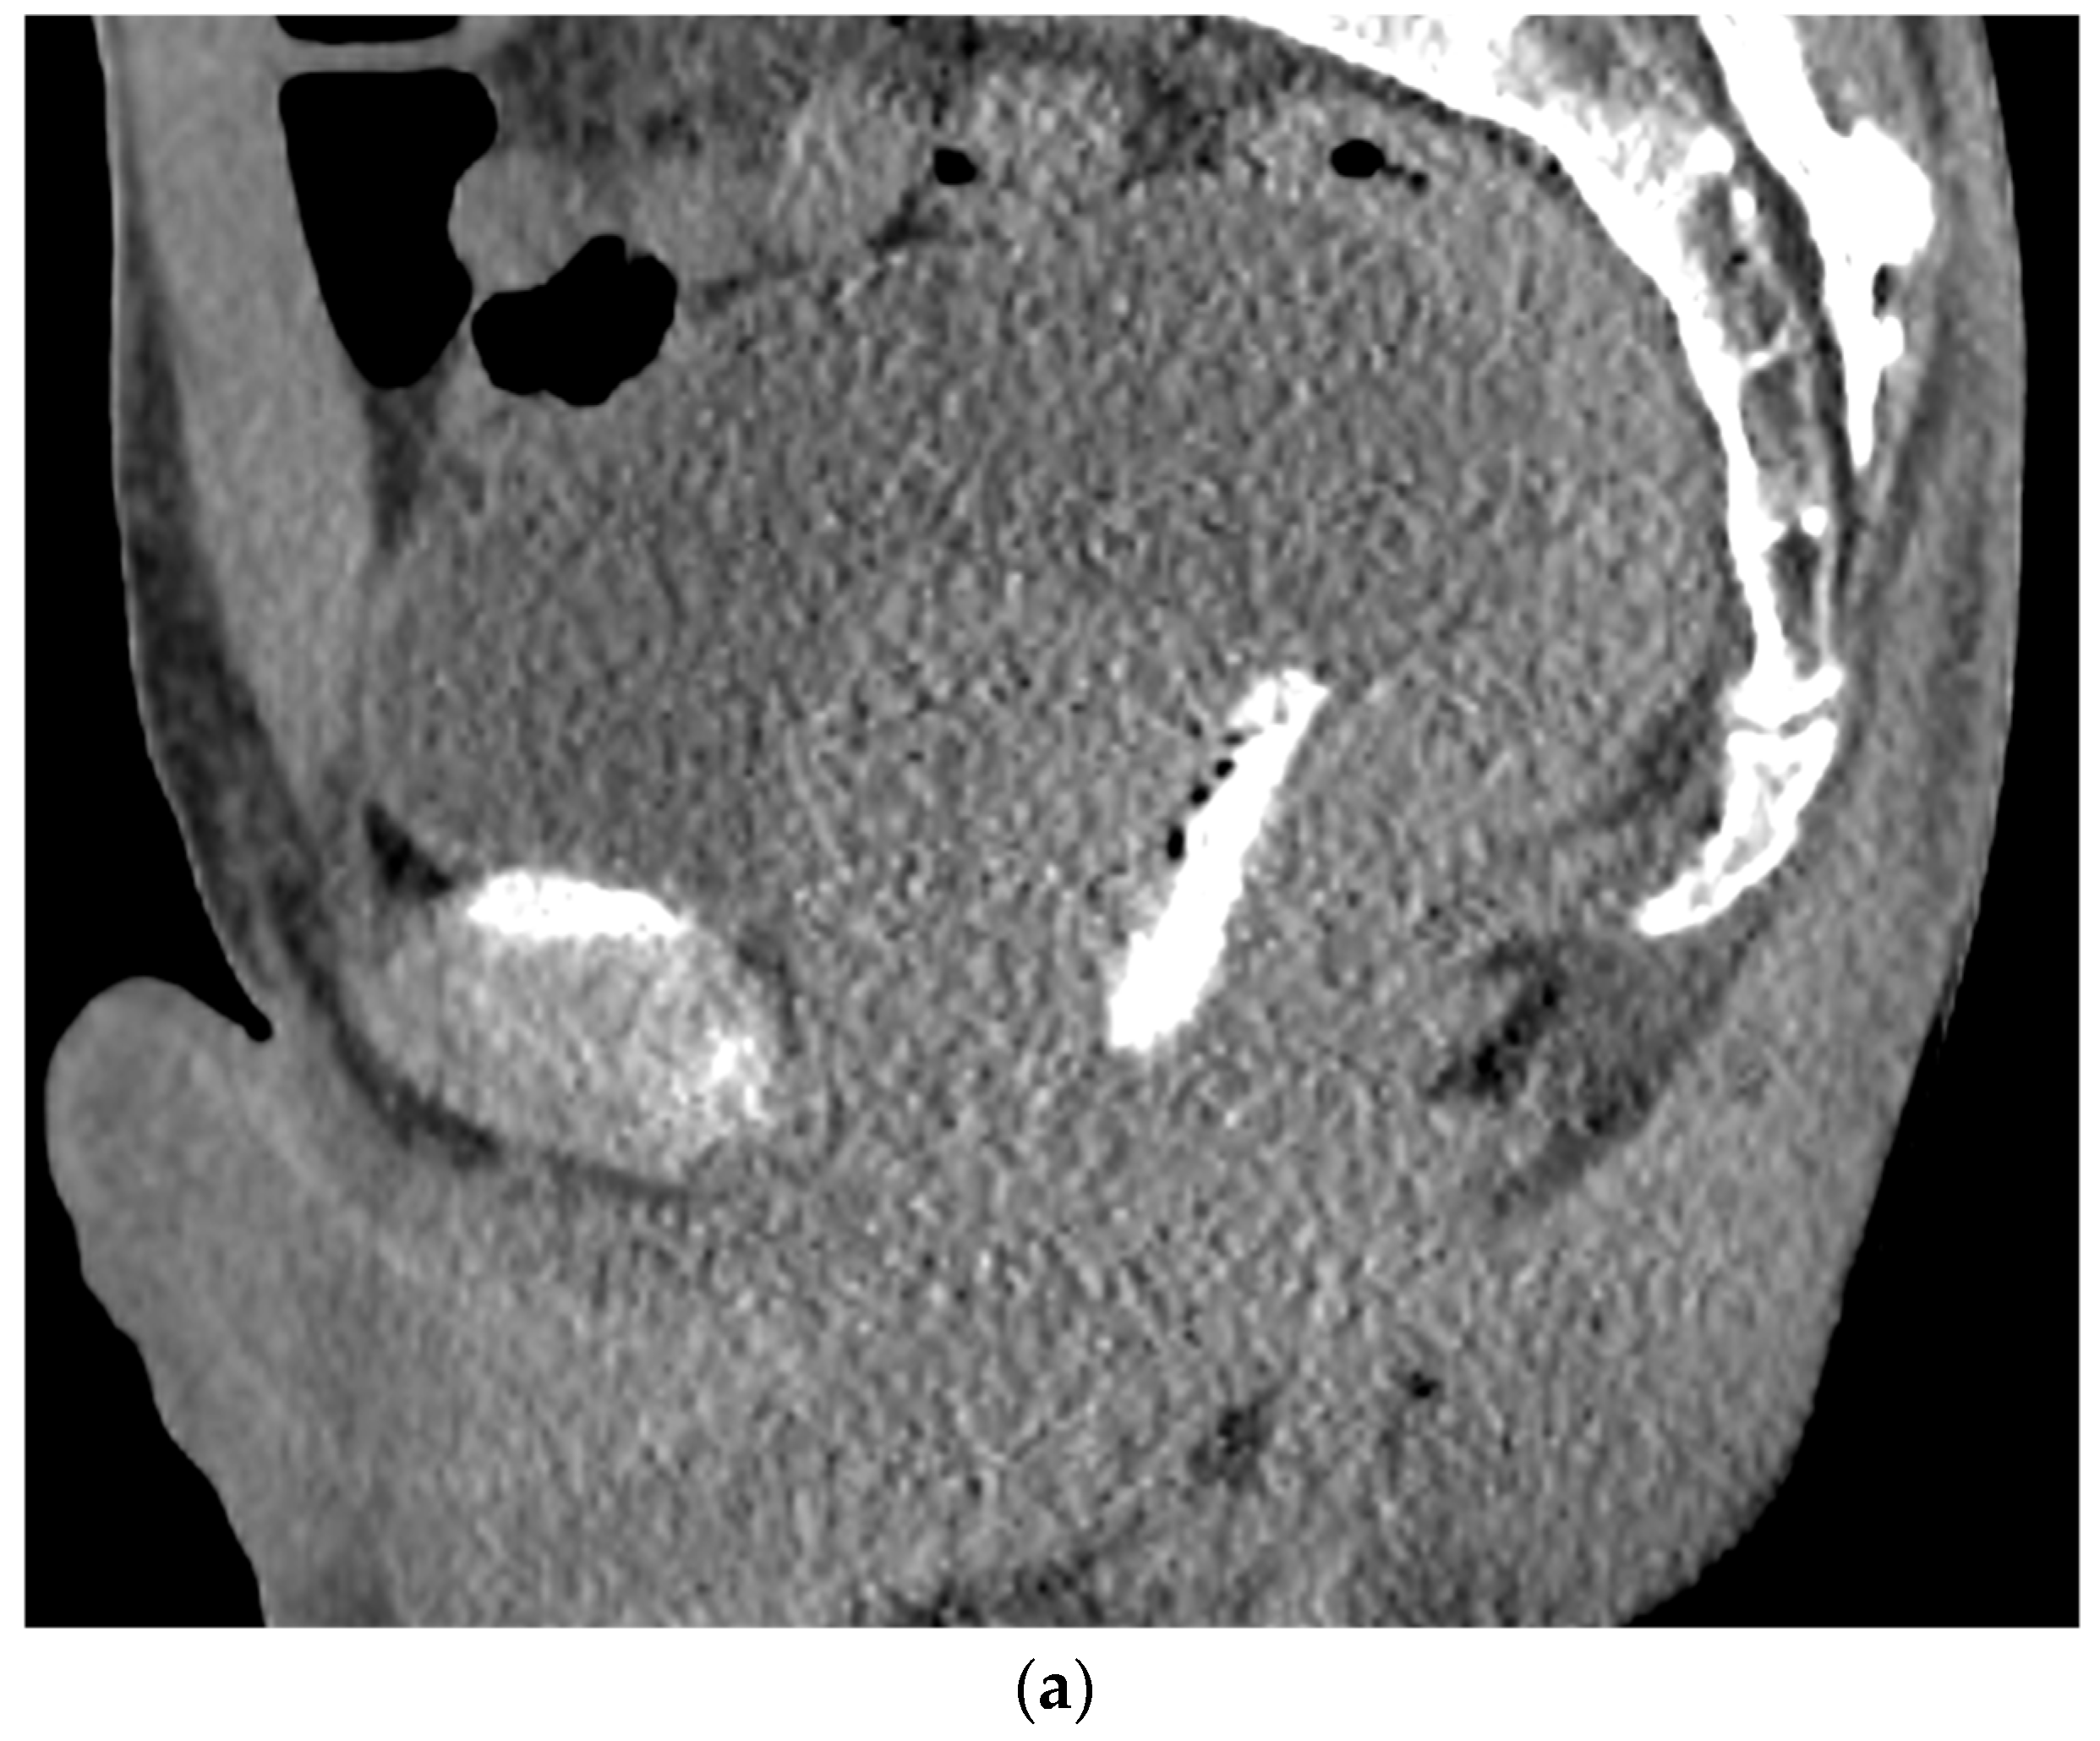

6. Placement

- Kamran, S.C.; McClatchy, D.M., 3rd; Pursley, J.; Trofimov, A.V.; Remillard, K.; Saraf, A.; Ghosh, A.; Thabet, A.; Sutphin, P.; Miyamoto, D.T.; et al. Characterization of an Iodinated Rectal Spacer for Prostate Photon and Proton Radiation Therapy. Pract. Radiat. Oncol. 2022, 12, 135–144. [Google Scholar] [CrossRef]

- SpaceOAR™ Vue System. 2022. Available online: https://www.bostonscientific.com/content/dam/bostonscientific/spaceoar/vue/URO-855204-AA%20SpaceOAR%20VUE_Brief%20Summary.pdf (accessed on 9 August 2022).

- SpaceOAR Vue™ Hydrogel. 2020. Available online: https://www.bostonscientific.com/content/dam/bostonscientific/spaceoar/vue/SpaceOAR-Vue-Hydrogel-Brochure.pdf (accessed on 9 August 2022).

- Brenneman, R.J.; Andruska, N.; Roy, A.; Waters, M.R.; Fischer-Valuck, B.W.; Schiff, J.P.; Goddu, S.M.; Henke, L.E.; Gay, H.A.; Baumann, B.C.; et al. Characterization of a Novel Radiopaque Perirectal Hydrogel Spacer for Prostate Cancer Radiotherapy. Int. J. Radiat. Oncol. Biol. Phys. 2021, 111, e536. [Google Scholar] [CrossRef]

- Conroy, D.; Becht, K.; Forsthoefel, M.; Pepin, A.N.; Lei, S.; Rashid, A.; Collins, B.T.; Lischalk, J.W.; Suy, S.; Aghdam, N.; et al. Utilization of Iodinated SpaceOAR Vue During Robotic Prostate Stereotactic Body Radiation Therapy (SBRT) to Identify the Rectal-Prostate Interface and Spare the Rectum: A Case Report. Front. Oncol. 2020, 10, 607698. [Google Scholar] [CrossRef]

- Gross, A.; Yuan, J.; Spratt, D.; Fredman, E. Case Report: Role of an Iodinated Rectal Hydrogel Spacer, SpaceOAR Vue, in the Context of Low-Dose-Rate Prostate Brachytherapy, for Enhanced Post-Operative Contouring to Aid in Accurate Implant Evaluation and Dosimetry. Front. Oncol. 2021, 11, 810955. [Google Scholar] [CrossRef]